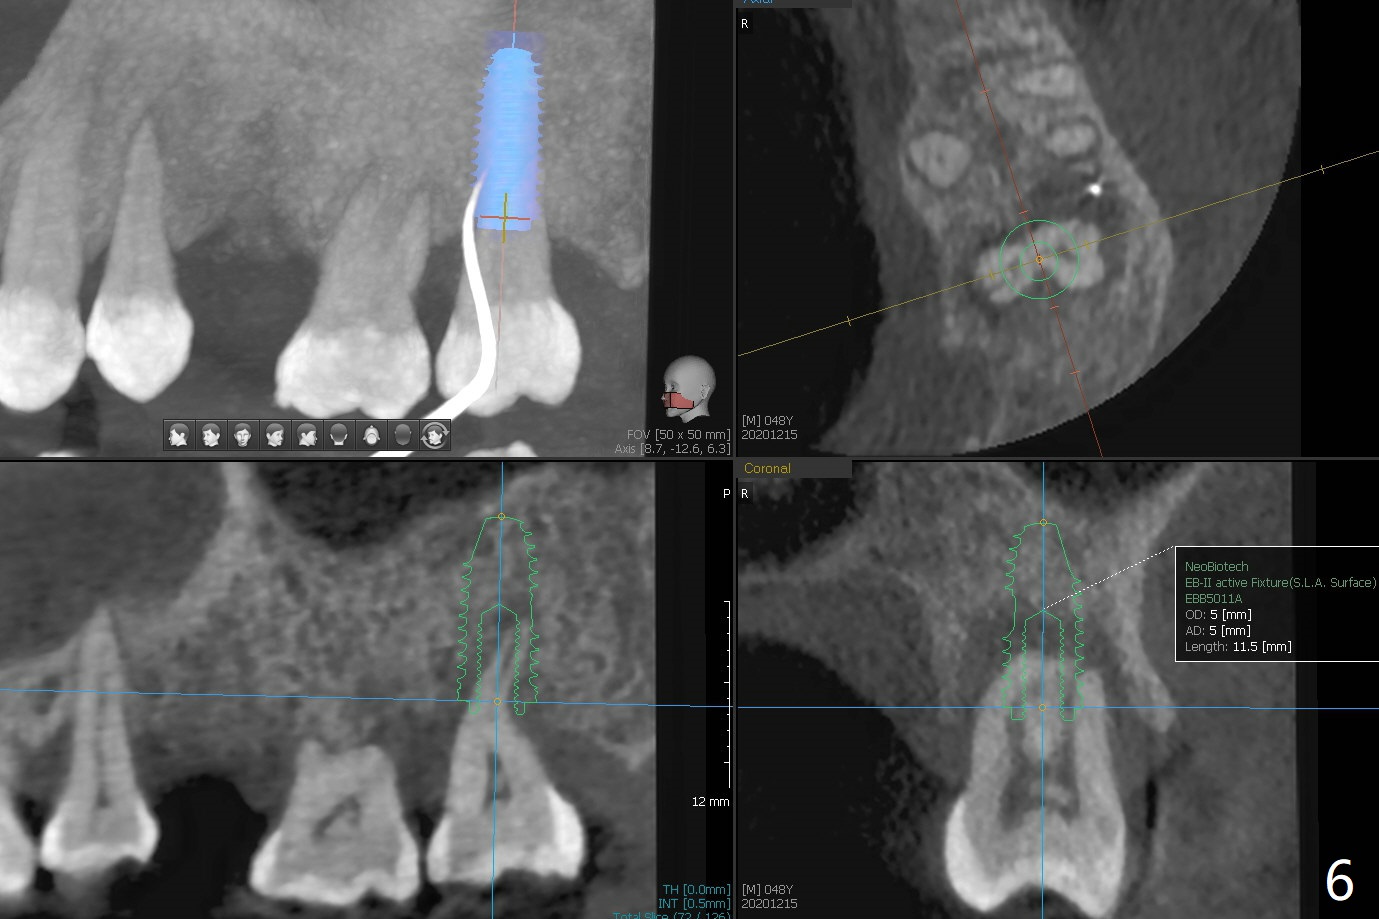

术后二周牙周敷料松动,取出后,伤口尚可(图三)。可能病人用右侧咀嚼,造成右上两个双尖牙松动疼痛,拔出后即刻种植修复,之后她能在右侧咀嚼,而食物撞击左上拔牙创疼痛,无法吃饭。术后三个月左上7疼痛,瘘道,插入牙胶尖(图四:*),根周阴影。其实腭侧根纵裂(图四,五:<),三个月已经发生(图二),可以即刻种植(图六),与5延期种植同时进行,使用导板。